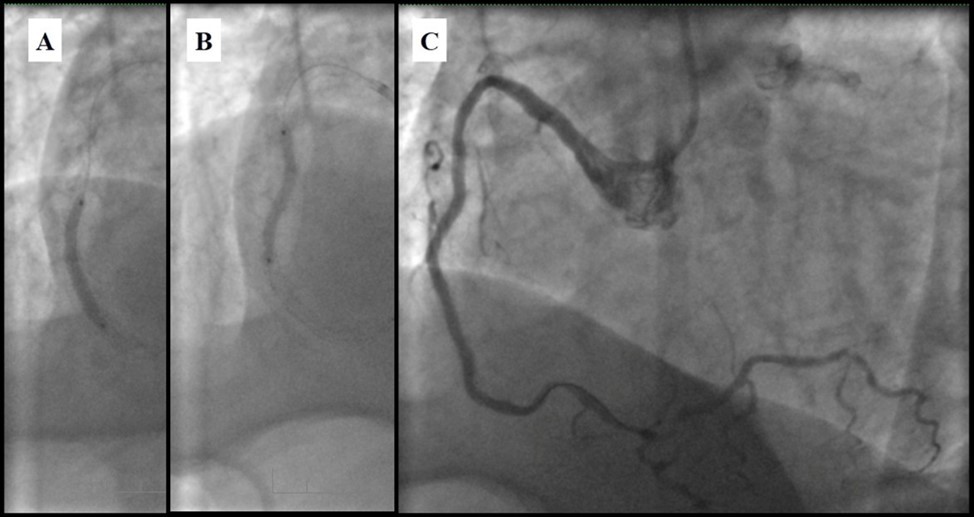

Angiography revealed rare anatomical variation LMCA quadrifurcation (Figure 1, Figure 2), 50% stenosis of the distal part of the LMCA, 40% stenosis of the ostial segment of left anterior descending (LAD) artery and diffuse prolonged 70-75-95% stenosis in mid-segment (Figure 3), 75% stenosis of the ostial segment of the circumflex (CX) artery, 75% stenosis of the ostial segment of the first marginal branch (OM1), 75-90% stenosis of the proximal segment of the intermediate artery (IMA), prolonged diffuse severe 90-95% stenosis of mid-segment of the right coronary artery (RCA) (Figure 4).

Figure 1.Quadrifurcation of the left main coronary artery

Figure 3.Prolonged diffuse severe 90-95% stenosis of mid-segment of the right coronary artery. A - Left anterior oblique 45° projection; B – Right anterior oblique 45° projection.

Figure 4.A - 50% stenosis of the distal segment of the LMCA; B - 70-75-95% stenosis in mid-segment of the LAD.